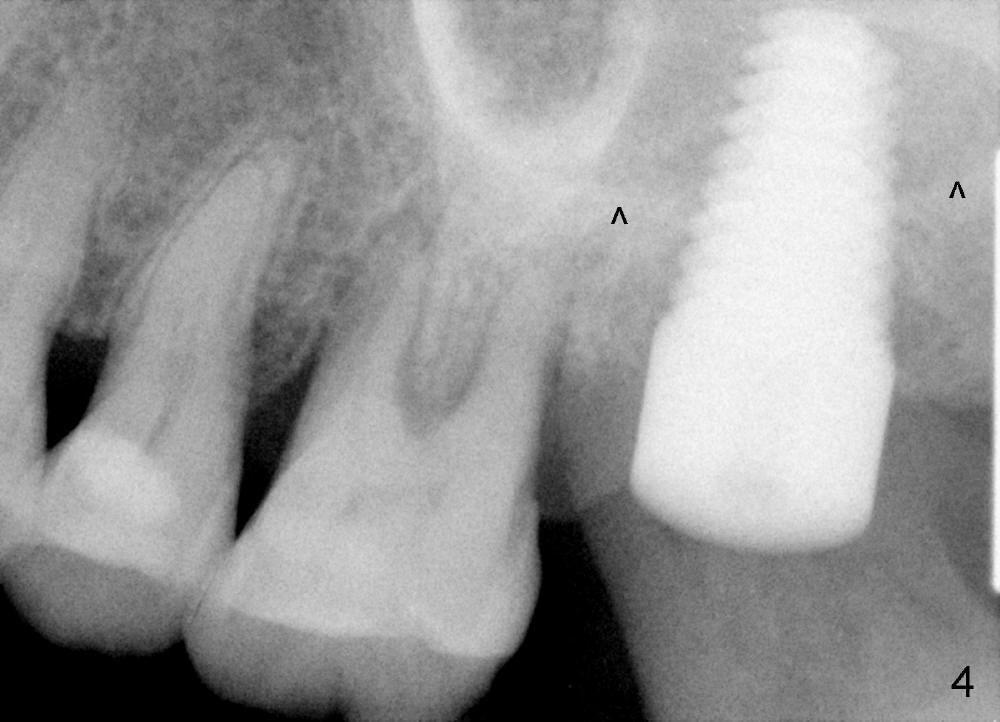

A 56-year-old female has recurrent infection and buccal gingival recession (Fig.1 *) after root canal therapy in the upper left 2nd molar (Fig.2). The extraction socket is single and large. Osteotomy forms by using a series of osteotomes (2-5 mm in diameter) mesiopalatal to the center of the socket. The sinus floor is thin (approximately 2-3 mm). The osteotomy is further enlarged by inserting 4.5-8 mm taps at the depth between 14 and 17 mm from the gingival margin. The last tap has barely achieved stability (Fig.3). It appears that the tap has almost obliterated the socket. Allograft is pushed into the sinus before placement of a 8x17 mm implant. The insertion torque is between 15 and 20 Ncm (Fig.4). The gingiva-level implant is slightly subgingival except buccal (Fig.5). To facilitate buccal gingival re-growth and cover the exposed implant surface, bone graft is placed subgingival (Fig.5 ^). The gingival sulcus is closed partially by placement of a thin strip of collagen membrane (not shown). The wound is protected by applying perio dressing.

Next time she returns 4.5 months postop, bone looks normal around the implant (Fig.7), whereas the buccal gingival recession appears to get worse with 1-2 implant thread exposure (Fig.8 >). To avoid this complication, the initial osteotomy should be placed as palatal as possible; when the implant is placed with gingival recession (Fig.5), soft tissue graft should be performed. The implant should be smaller.

Model study shows that the implant is placed distally (Fig.9,11) in addition to buccal implant exposure (Fig.10 arrowheads). Postop, the patient complains of upper left discomfort, which is more likely associated with furcal infection of the tooth #14. The symptom disappears after use of water pik. Panoramic X-ray is taken 6 months post cementation (Fig.12).